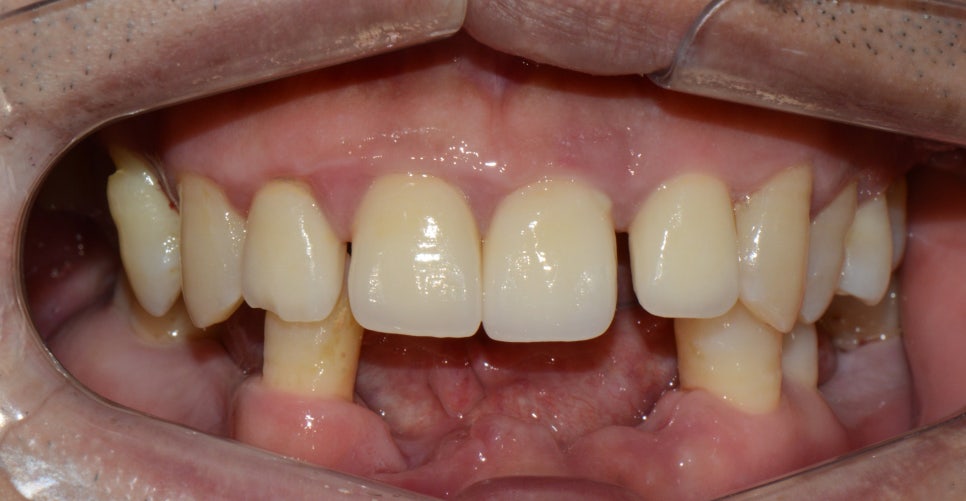

앞니 교정 + 윗쪽 임플란트

앞니 벌어진 공간이 예쁘게 잘 배열되었습니다.

본인치아를 살리고 교정으로 벌어진 공간을 닫은 상태

교정은 3~4개월이면 끝납니다.